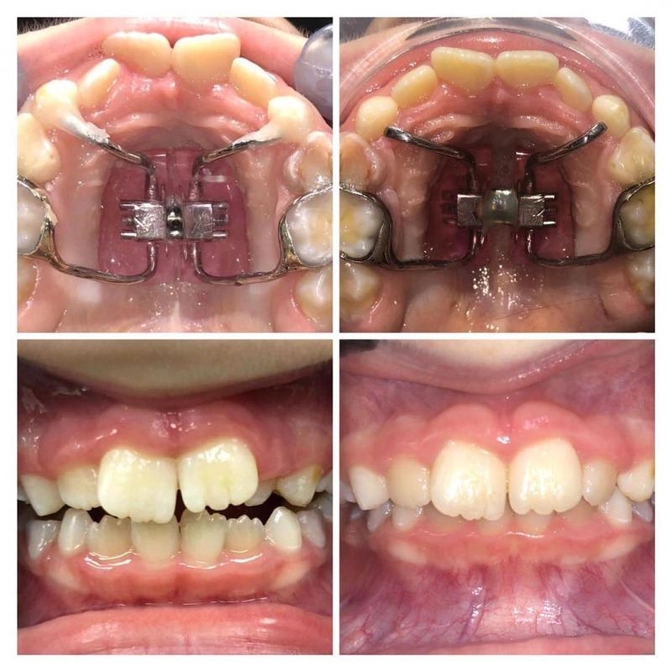

Смотрите, что было «до» и какой результат спустя 4 месяца.

Причем из них активный период лечения - всего 3 недели!

Такого результата смогли добиться с помощью аппарата Haas.

1. Здесь было проведено быстрое небное расширение.

2. Мы добились значительного увеличения места для фронтальной группы зубов верхней челюсти.

3. Простимулировали рост и развитие нижнего зубного ряда.

4. Расширили носовые ходы, улучшив дыхание.

5. Дальше планируем поработать над эстетикой, немного расширить челюсть с помощью дуги Питтса.

Поставим «детскую» брекет-систему 2*4 всего на пару месяцев.